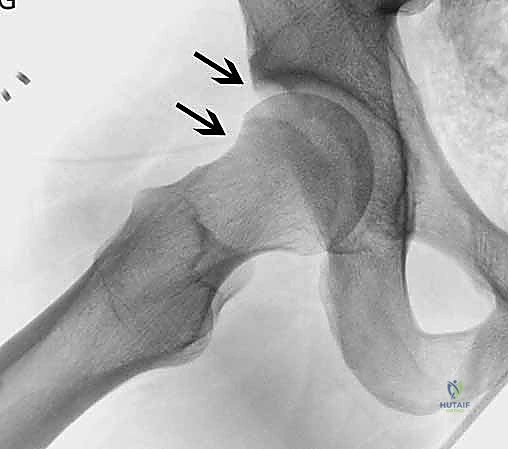

1. انحشار الكامة (Cam Impingement)

يحدث هذا النوع عندما لا يكون رأس عظم الفخذ كروياً بشكل مثالي. بدلاً من ذلك، تتكون نتوءات عظمية إضافية عند منطقة التقاء رأس وعنق الفخذ. هذا الشكل غير الدائري يجعله يحتك بقوة بحافة التجويف (الحُق) أثناء الحركة، مما يؤدي إلى "كشط" وتمزيق الغضروف والشفا الحقي. هذا النوع شائع جداً بين الشباب والرياضيين الذكور.

- الأشعة السينية (X-rays): لتقييم شكل العظام، قياس "زاوية ألفا" (Alpha Angle)، وتحديد وجود نتوءات الكامة أو الكماشة.